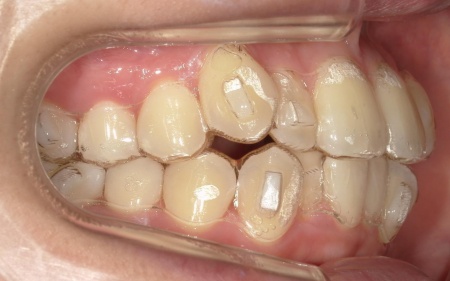

歯並びを改善する方法として、透明なマウスピースを段階的に交換しながら歯を動かしていくインビザラインコンプリヘンシブパッケージによる矯正治療を提案し、同意いただきました。

まず、患者様専用のマウスピースを作製し、1日一定時間装着していただくようご案内しました。

マウスピースは定期的に新しいものへ交換しながら、少しずつ歯を移動させています。

治療と並行して、歯と歯の間にスペースを作るためのIPRを適切なタイミングで実施しました。また、噛む力が強い傾向が見られたため、奥歯の噛み込みを抑え、歯をスムーズに動かすために「バイトランプ」と呼ばれる小さな突起をマウスピースの上の前歯の裏側に設置しています。